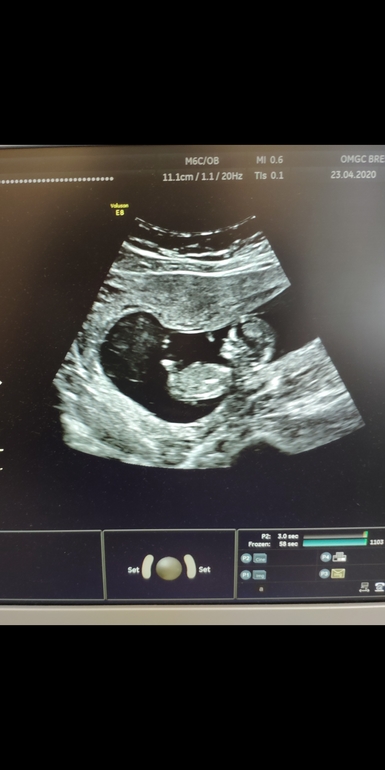

Наш первый скрининг

Итак , малыш очень активный , гонялись датчиком , трясли ,чтоб поварачивался , но все рассмотрели. Идём ровно по сроку .

КТР 57 мм

Твп 1.1

Носовая косточка есть

Все на месте ,здоровый малыш.

Хорион по передней стенке

Показали на экране , попросила сфоткать на телефон ,она разрешила ,я от счастья забыла спросить может и пол виден,предположительно. Но убежала счастливая на кровь 🤭 Ладно ,через 3-4 недели точно узнаем.